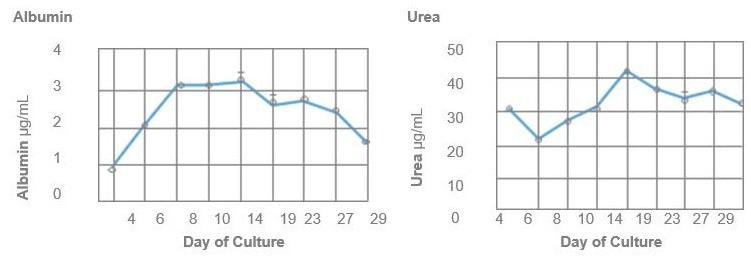

Liver function

The chart below offers a comparison of albumin secretion levels between HEPATOPAC culture and hepatocytes in suspension, highlighting the prolonged viability of the HEPATOPAC culture system.

Image Credit: BioIVT